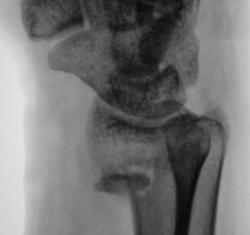

У пациентки снят ГИПС. Пациентка направлена на рентгенографию лучезапястного сустава с целью рентгенологического подтверждения консолидации.

Настораживает повышенная плотность отдельно лежащего фрагмента по передней поверхности метафиза луча на фоне  легкой общей минералопении, признаков формирования костной мозоли не видно - есть основания зподозрить нарушение его трофики с последующим формированием секвестра.

Консолидации нет.